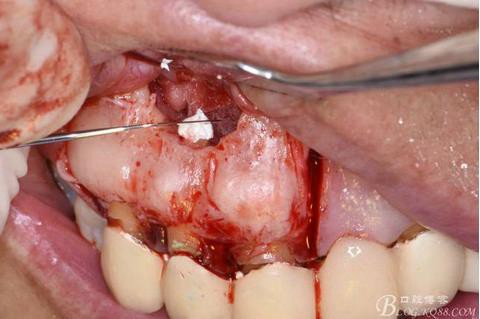

圖10.剝離囊壁

圖11.摘除囊壁后形成的骨腔